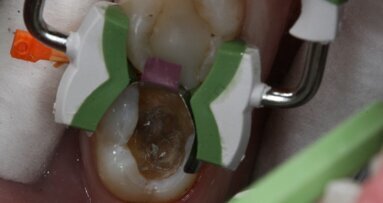

Viene posizionata una matrice Fusion FX175 e inserito un cuneo Fusion FXOR da vestibolare, per favorire la chiusura della matrice nell’angolo tra gradino cervicale e parete assio-pulpare vestibolare, resa difficile dalla rotazione dell’elemento 1.5 (Fig. 6). Si posiziona l’anello separatore FX400 - si noti il perfetto adattamento della matrice alle pareti assiali e al gradino cervicale. Quest’ultimo grazie soprattutto all’azione delle alette in silicone del cuneo (Fig. 7). Un’altra inquadratura evidenzia la profondità della cavità pulita (Fig. 8).

Nella figura 9 è mostrata la visione vestibolare dopo la fase di applicazione del bonding, che viene steso con un leggero soffio d’aria e contemporaneamente aspirato per favorire la fuoriuscita degli eccessi. La fase adesiva termina con la polimerizzazione di un sottile strato di composito fluido (Fig. 10).Successivamente viene ricostruita la parete interprossimale e la cresta marginale con un unico apporto di composito (Fig. 11). La figura 12 illustra il restauro al termine della stratificazione e dell’applicazione del supercolore, con la rimozione dell’anello separatore dopo la polimerizzata della parete interprossimale. Nella figura 13 possiamo vedere il restauro al termine della sgrossatura e rifinitura con dischetti abrasivi, frese diamantate 40 micron e gommini browny; si noti come la cresta marginale sia facilmente rifinibile grazie alla guida della matrice anatomica, senza che l’area di contatto venga toccata dagli strumenti.